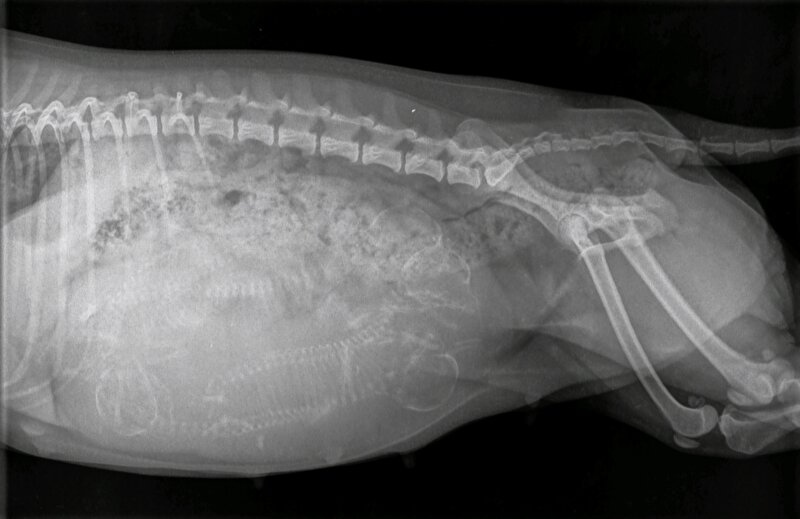

Het kan ook wel. Maar de ervaring is dat je dan gewoon een slecht beeld hebt. Als je wacht tot 55+ dagen zie je het veel duidelijker. En daar doe je t voor..

En altijd van 2 zijkanten foto’s maken. Soms liggen pups wat verstopt en dan zie je ze vanaf de ene kant niet liggen.

En de reden dat ik daar over “zeur” is dat de baarmoeder een vorm van een Y heeft. Dat wil zeggen: 1 baarmoederhoorn linkerzijde hond en 1 rechterzijde. Op de eerste foto lijkt een 5e aanwezig, die op de 2e foto bijna niet meer te zien is. Wat kan betekenen dat er nog steeds een nr 5(of6) aanwezig is, want wat je ook op de foto ziet is een gevulde darm. Ter hoogte van de 3 schedels is het dus te vol van ontlasting om een goed beeld te krijgen.

Maar vooraan vind ik het beeld ook te vaag om duidelijk te zien wat daar zit. Ik zou dus zeker nieuwe foto’s maken en dan van beide kanten.

Het zijn in ieder geval minimaal 4 pups, maar het zou me niets verbazen als er straks nog meer uitkomen.

floorsil schreef:Volg gewoon even mee.maar als ik hoofdjes of ruggengraten tel ik er 6 . Hoe zit dat? Heel veel succes met de laatste loodjes.